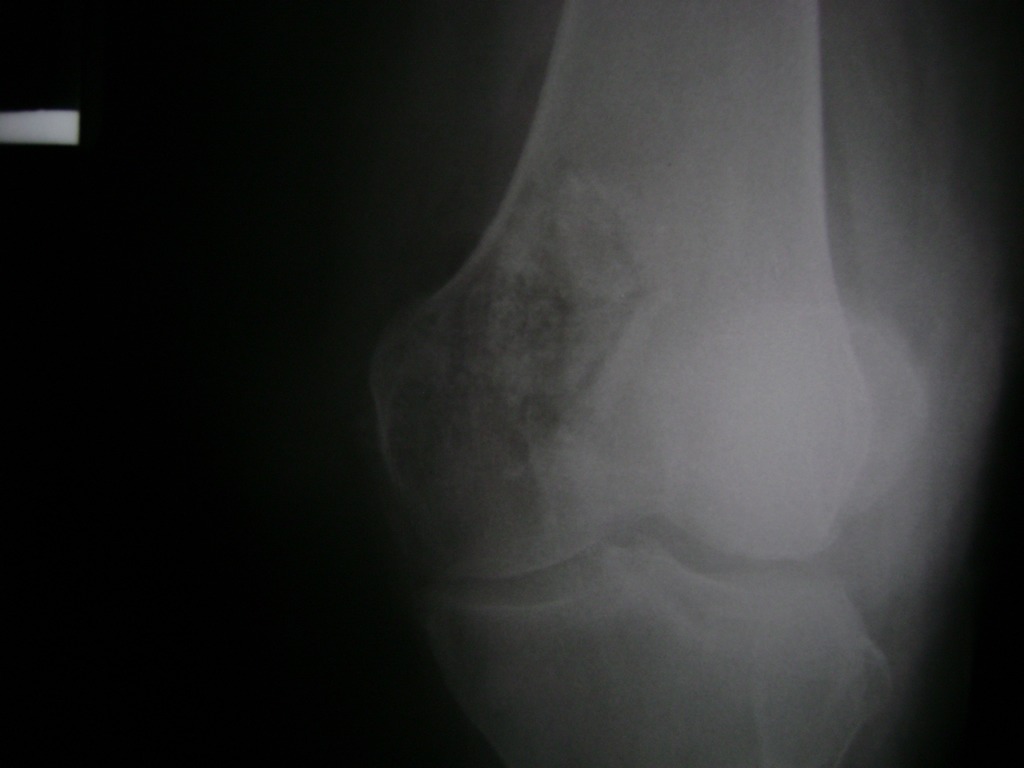

Cirugías de Húmero - Rodilla

La artroscopia de rodilla es un cirugía en el cual la estructura interna de la articulación es examinada ya sea para realizar un diagnostico o para realizar un tratamiento, este procedimiento se realiza utilizando un instrumento parecido a un pequeño tubo llamado artroscopio.